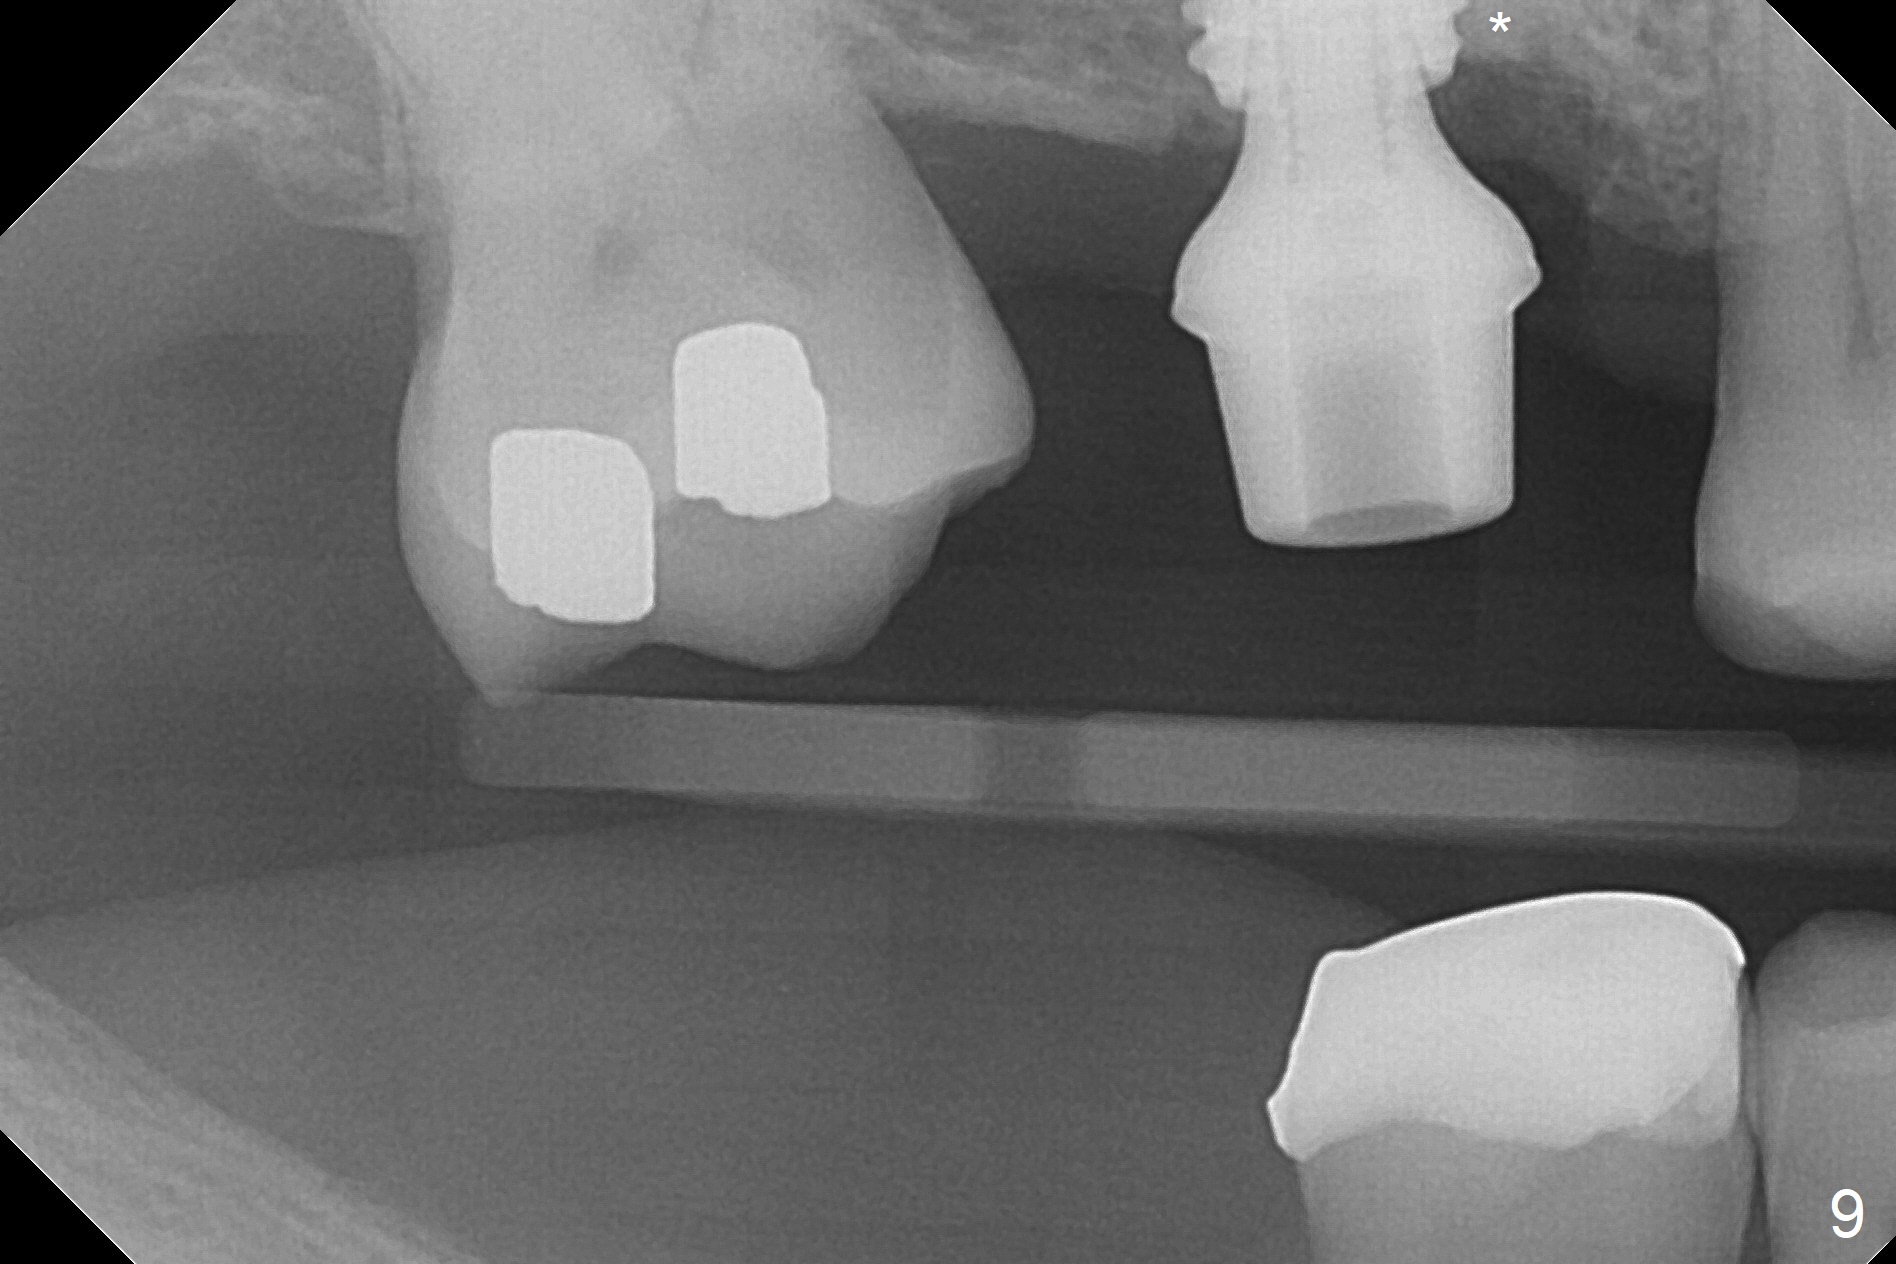

The palatal cusp of the affected 2nd premolar is apparently rotated distal (Fig.1). It is more obvious for the socket (Fig.2): the palatal (P) portion of the socket is more distal than the buccal (B) one. When the gauze is removed (Fig.3), Lindamann bur is used to remove the disto(D)palatal bone of the socket (data not shown), followed by starter drill in the DP wall obliquely (Fig.3'). Once the drill enters the bone for 1-2 mm, the bur is straightened and pushed slightly distal (Fig.3''). Fig.4 shows a parallel pin distal (overcorrect) to the original socket (Fig.4 red dashed line). Sequential osteotomy is conducted until 3.8x13 mm drill for 18 mm (Fig.5): note the 2 steps of the osteotomy (red lines). Since the apical portion of the osteotomy is larger than the drill, a larger implant than expected (5x16 mm) is placed. The implant ends up in the middle of the edentulous area (due to the stepped osteotomy; Fig.6-9; >60 Ncm). Vera allograft is placed (Fig.7-9 *) prior to and after placement of a 6.5x4(3) mm abutment (Fig.8-10). The remaining socket opening is sealed with a piece of Collagen plug (Fig.10 *). The socket is then closed by an immediate provisional (Fig.11 P). The abutment is retightened 2 months postop (Fig.12,13). The crown is cemented 4.5 months postop. Panoramic X-ray and CT are taken nearly 7 months post cementation (Fig.14,15) when the patient is ready for #30 implant guide preparation.